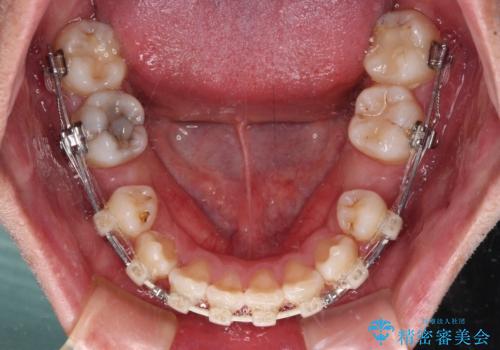

- 八重歯と上顎前歯の変色を気にして来院された患者様です。

上下ともに八重歯が顕著であったため、上下左右の第一小臼歯4本を抜歯し、ワイヤー装置での抜歯矯正を行うこととしました。

前歯は根管治療が必要な歯を事前に根管治療を行い、矯正治療後にオールセラミッククラウンにて補綴治療を行うこととしました。